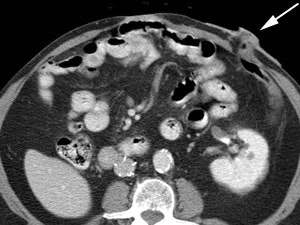

|

Benign adrenal lesion with FDG uptake: The patient shown below had a left adrenal mass which had remained stable for 2 years (white arrow). The stability over time and CT features would be consistent with a benign adrenal lesion- likely an adenoma. Note the marked FDG uptake within the mass on PET imaging (black arrows). Benign adrenal adenomas can accumulate FDG resulting in false positive exams. The use of PET/CT has been shown to improve the specificity of the PET exam. |

|

|